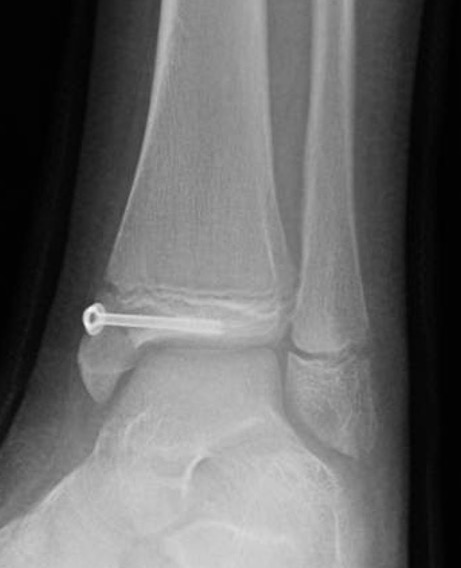

Operative management

Indication

Displaced articular fracture > 2 mm

Technique

Anterior approach between EHL and EDL

- reduce fracture with large reduction forceps

- epiphyseal screw from lateral to medial / medial to lateral

- metaphyseal AP screw into Thurston-Holland fragment